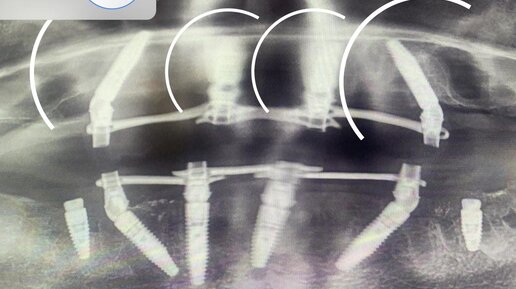

Гришенина Юлия Валерьевна - главный врач, челюстно-лицевой хирург клиники "Дентал Платс"